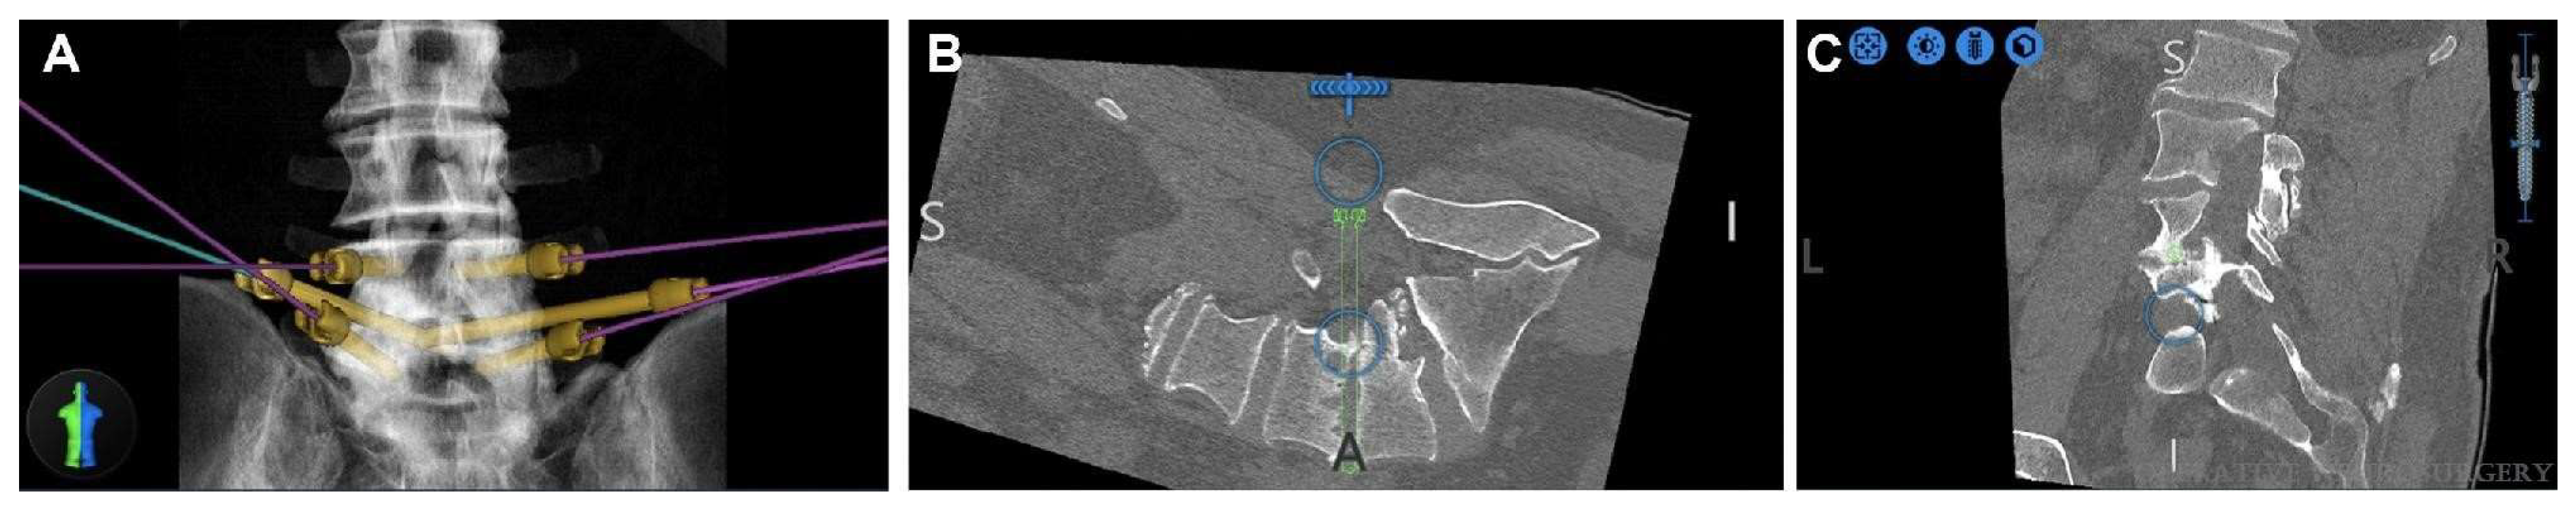

- Dalton, T.; Sykes, D.; Wang, T.Y.; Donnelly, D.; Than, K.D.; Karikari, I.O.; Goodwin, C.R.; Gupta, D.K.; Wiggins, W.F.; Abd-El-Barr, M.M. Robotic-Assisted Trajectory Into Kambin’s Triangle During Percutaneous Transforaminal Lumbar Interbody Fusion-Initial Case Series Investigating Safety and Efficacy. Oper. Neurosurg. 2021, 21, 400–408. [Google Scholar] [CrossRef] [PubMed]

- Lee, N.J.; Khan, A.; Lombardi, J.M.; Boddapati, V.; Park, P.J.; Mathew, J.; Leung, E.; Mullin, J.P.; Pollina, J.; Lehman, R.A. The accuracy of robot-assisted S2 alar-iliac screw placement at two different healthcare centers. J. Spine Surg. 2021, 7, 326–334. [Google Scholar] [CrossRef] [PubMed]

- Laratta, J.L.; Shillingford, J.N.; Lombardi, J.M.; Alrabaa, R.G.; Benkli, B.; Fischer, C.; Lenke, L.G.; Lehman, R.A. Accuracy of S2 Alar-Iliac Screw Placement Under Robotic Guidance. Spine Deform. 2018, 6, 130–136. [Google Scholar] [CrossRef] [PubMed]

- Shillingford, J.N.; Laratta, J.L.; Park, P.J.; Lombardi, J.M.; Tuchman, A.; Saifi, C.; Lehman, R.A., Jr.; Lenke, L.G. Human versus Robot: A Propensity-Matched Analysis of the Accuracy of Free Hand versus Robotic Guidance for Placement of S2 Alar-Iliac (S2AI) Screws. Spine 2018, 43, E1297–E1304. [Google Scholar] [CrossRef] [PubMed]

- Park, C.; Crutcher, C.; Mehta, V.A.; Wang, T.Y.; Than, K.D.; Karikari, I.O.; Goodwin, C.R.; Abd-El-Barr, M.M. Robotic-assisted percutaneous iliac screw fixation for destructive lumbosacral metastatic lesions: An early single-institution experience. Acta Neurochir. 2021, 163, 2983–2990. [Google Scholar] [CrossRef] [PubMed]